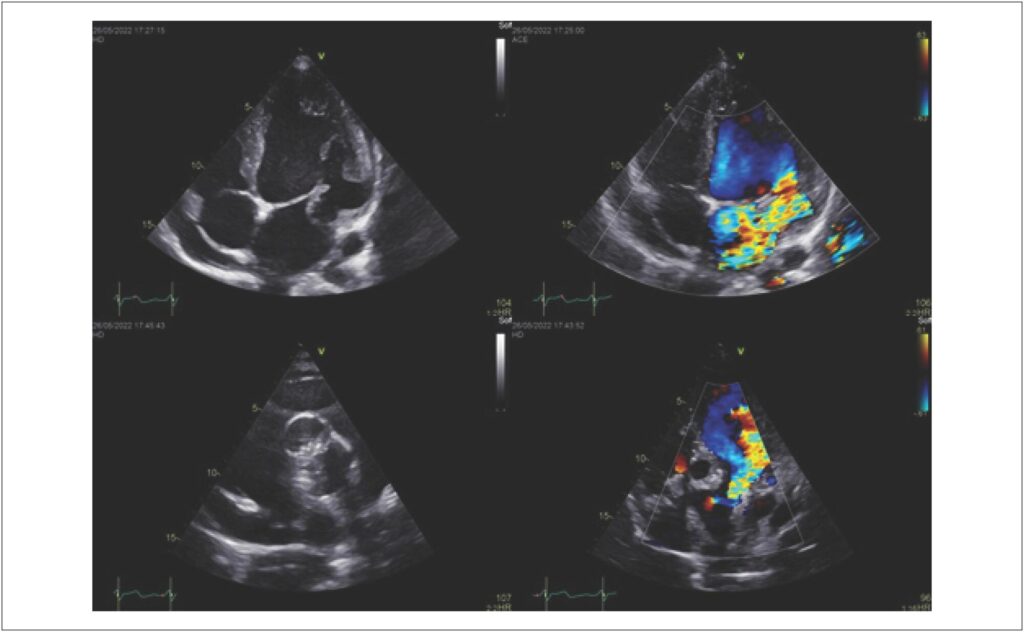

Aneurisma Subvalvar Mitral e Aórtico Idiopáticos em Paciente Jovem

Aneurismas do ventrículo esquerdo tem a doença arterial coronariana como sua principal etiologia. Dentre eles, existem tipos mais raros, como aqueles nas regiões subvalvares de origem idiopática. Nesse artigo, descrevemos o caso de um paciente com histórico de correção de um aneurisma subvalvar aórtico e outro no Seio de Valsalva, que se apresenta com novo aneurisma subvalvar mitral.